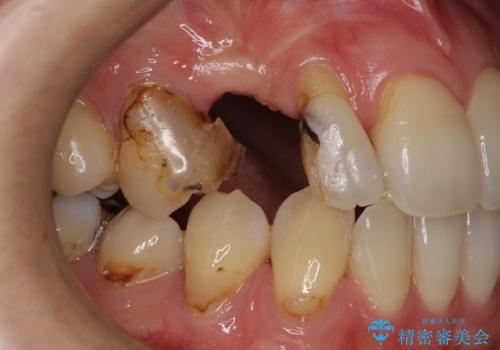

- 右上の歯はもともとなかったが、ブリッジにするのが嫌でプラスチックの歯を応急的に接着剤でつけていたのがとれてしまったとのことでした。

接着剤で留めてある周りが、虫歯になってしまっていました。

しっかり虫歯を取ったうえで、清掃性の高いブリッジにしていくことをおすすめしました。

初めはブリッジにすることに抵抗があったようですが、とりあえずでくっつける汚い状態ですと虫歯のリスクが非常に高いことをご説明しました。

右上④3②①ブリッジの設計としました。